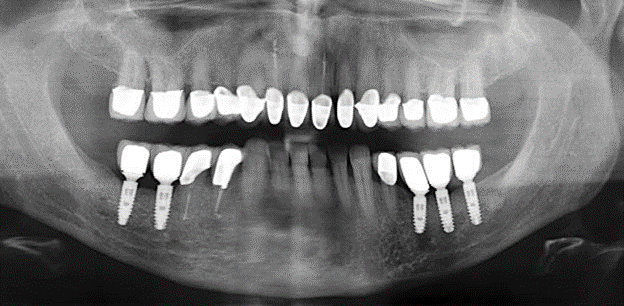

A 52-year-old patient presented in our clinic for the first time in 2004 following tooth loss in the third quadrant, expressing a desire for a new prosthetic restoration. Periodontal and radiological diagnostics revealed the need for extensive periodontological treatment. In addition, teeth 48, 28 and 27 were attributed a very poor prognosis and were subsequently extracted (Fig. 1). Following the successfully completed, systematic periodontological treatment, a fixed dental implant was inserted with the introduction of five implants in tooth regions 35, 36, 37, 46 and 47. Prosthetic treatment of the natural teeth was effected with veneered zirconium dioxide ceramic crowns; the implants were composed of two-piece, individual zirconium dioxide abutments and similarly veneered crowns made of a zirconium dioxide ceramic (Cercon base colored, Dentsply Sirona Lab). Definitive insertion of the prosthetic restoration occurred in 2005.

The ten-year check-up revealed no indications of advancing clinical attachment loss or peri-implant bone substance loss (Fig. 3).